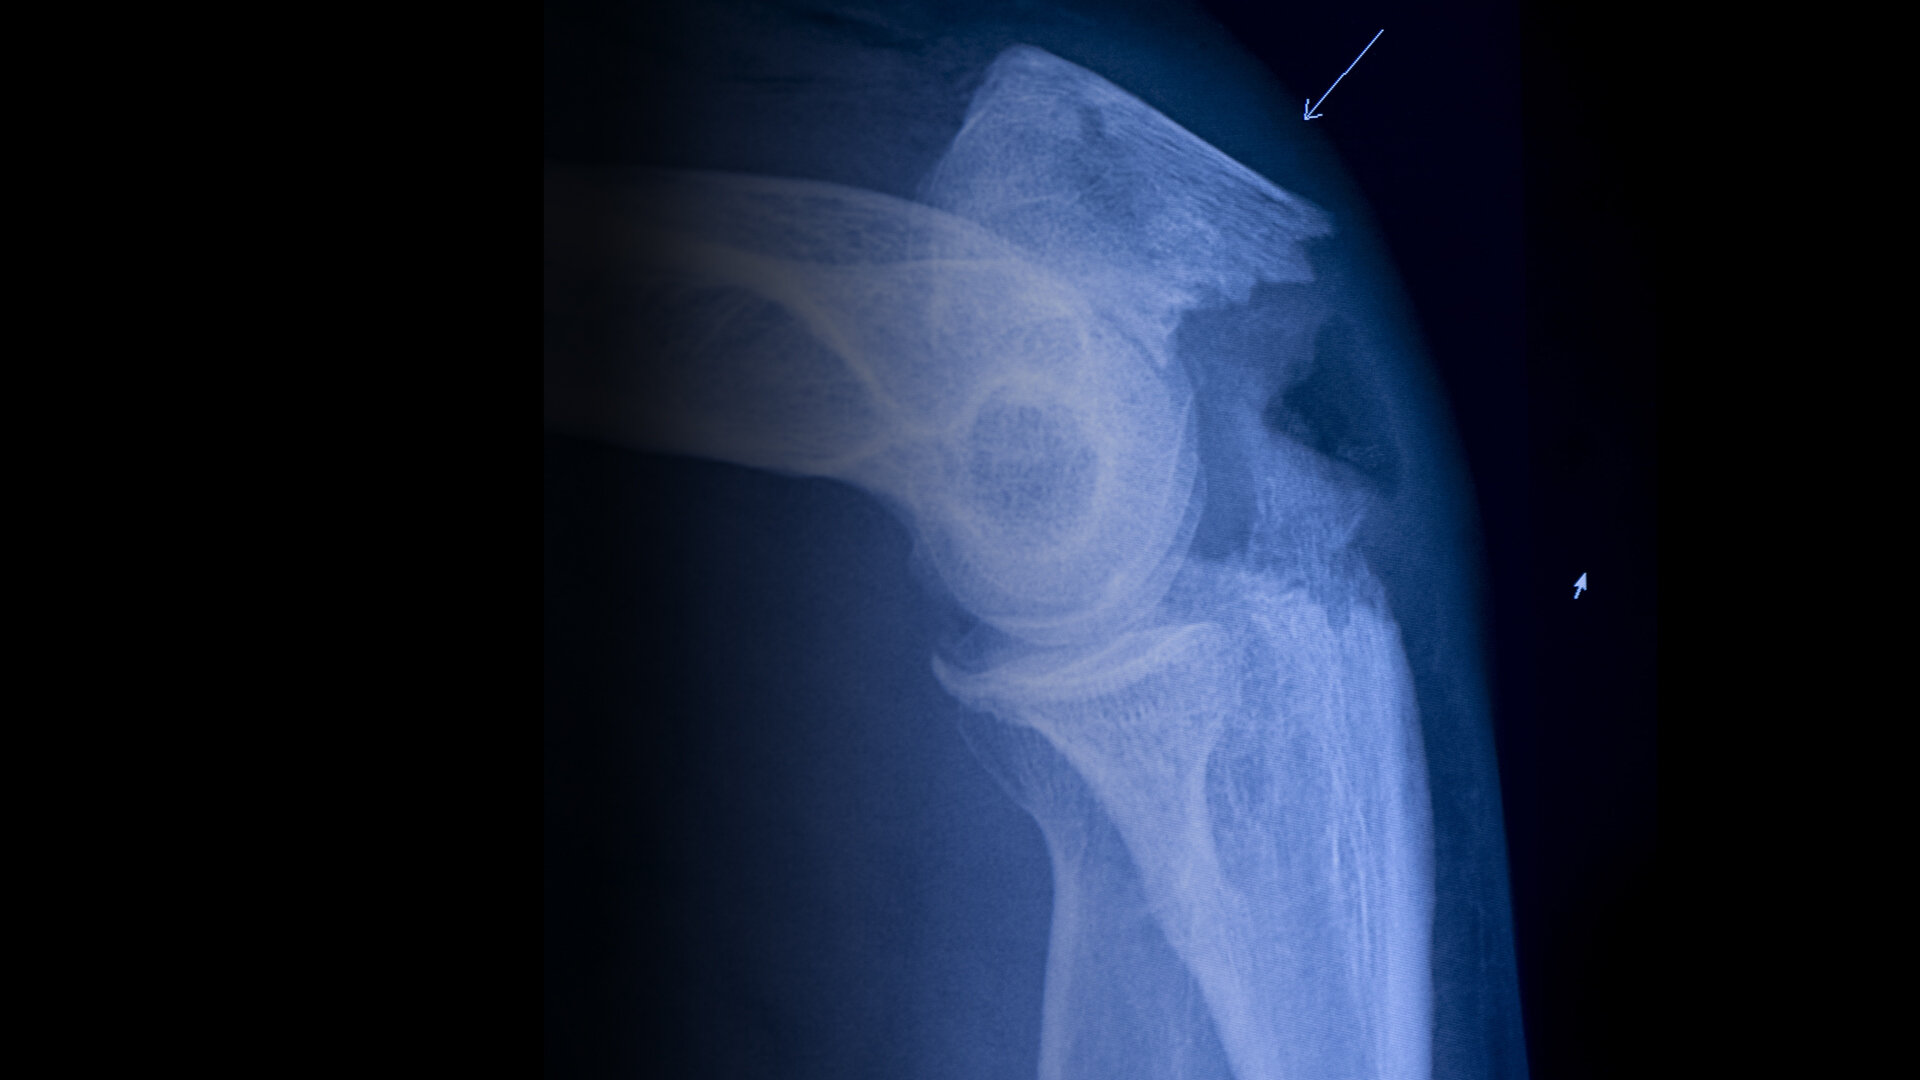

#Fall Når eldre mennesker faller, starter problemene.Leder, Barth TholensEn høy pris for et lite uhellLeder SykepleienHvorfor snakke om fall?Regjeringen mislyktes i å redusere antall hoftebruddNyheter– Jeg er redd for å bli rullestolavhengigNyheterPasientene får effektiv oppfølging på osteoporoseklinikkenFagutviklingHvorfor faller eldre?FagutviklingVil redusere hoftebrudd med minst 500 i året med egne bruddsykepleiereNyheter– Jeg har fått en psykisk knekkNyheterFallpoliklinikk: Sykepleier Elisabet Sigurjonsdottir jakter snubletråder hver dagNyheterReduserte hoftebrudd med 40 prosent på fire årNyheter– Jeg har begynt å se meg over skuldra når jeg er i byenNyheterHva innebærer en fallskade?Fagutvikling– Tenk fallforebygging tidligNyheterJudoklubben lærer eldre å falle som en bananNyheterDa jeg ikke var derDebatt– Smerten var så grusom at jeg nesten ble bedøvdNyheterHva gjør vi når eldre har falt?Fagutvikling– Jeg savner å gå på ski. Sykle, løpeNyheterKan noen fall skyldes medisinene?Nyheter10 millioner kroner utbetalt etter fallskaderNyheterSensorene varsler når «Anna» står oppNyheterUtgave på papirKjøp Sykepleien på papir herNyheter